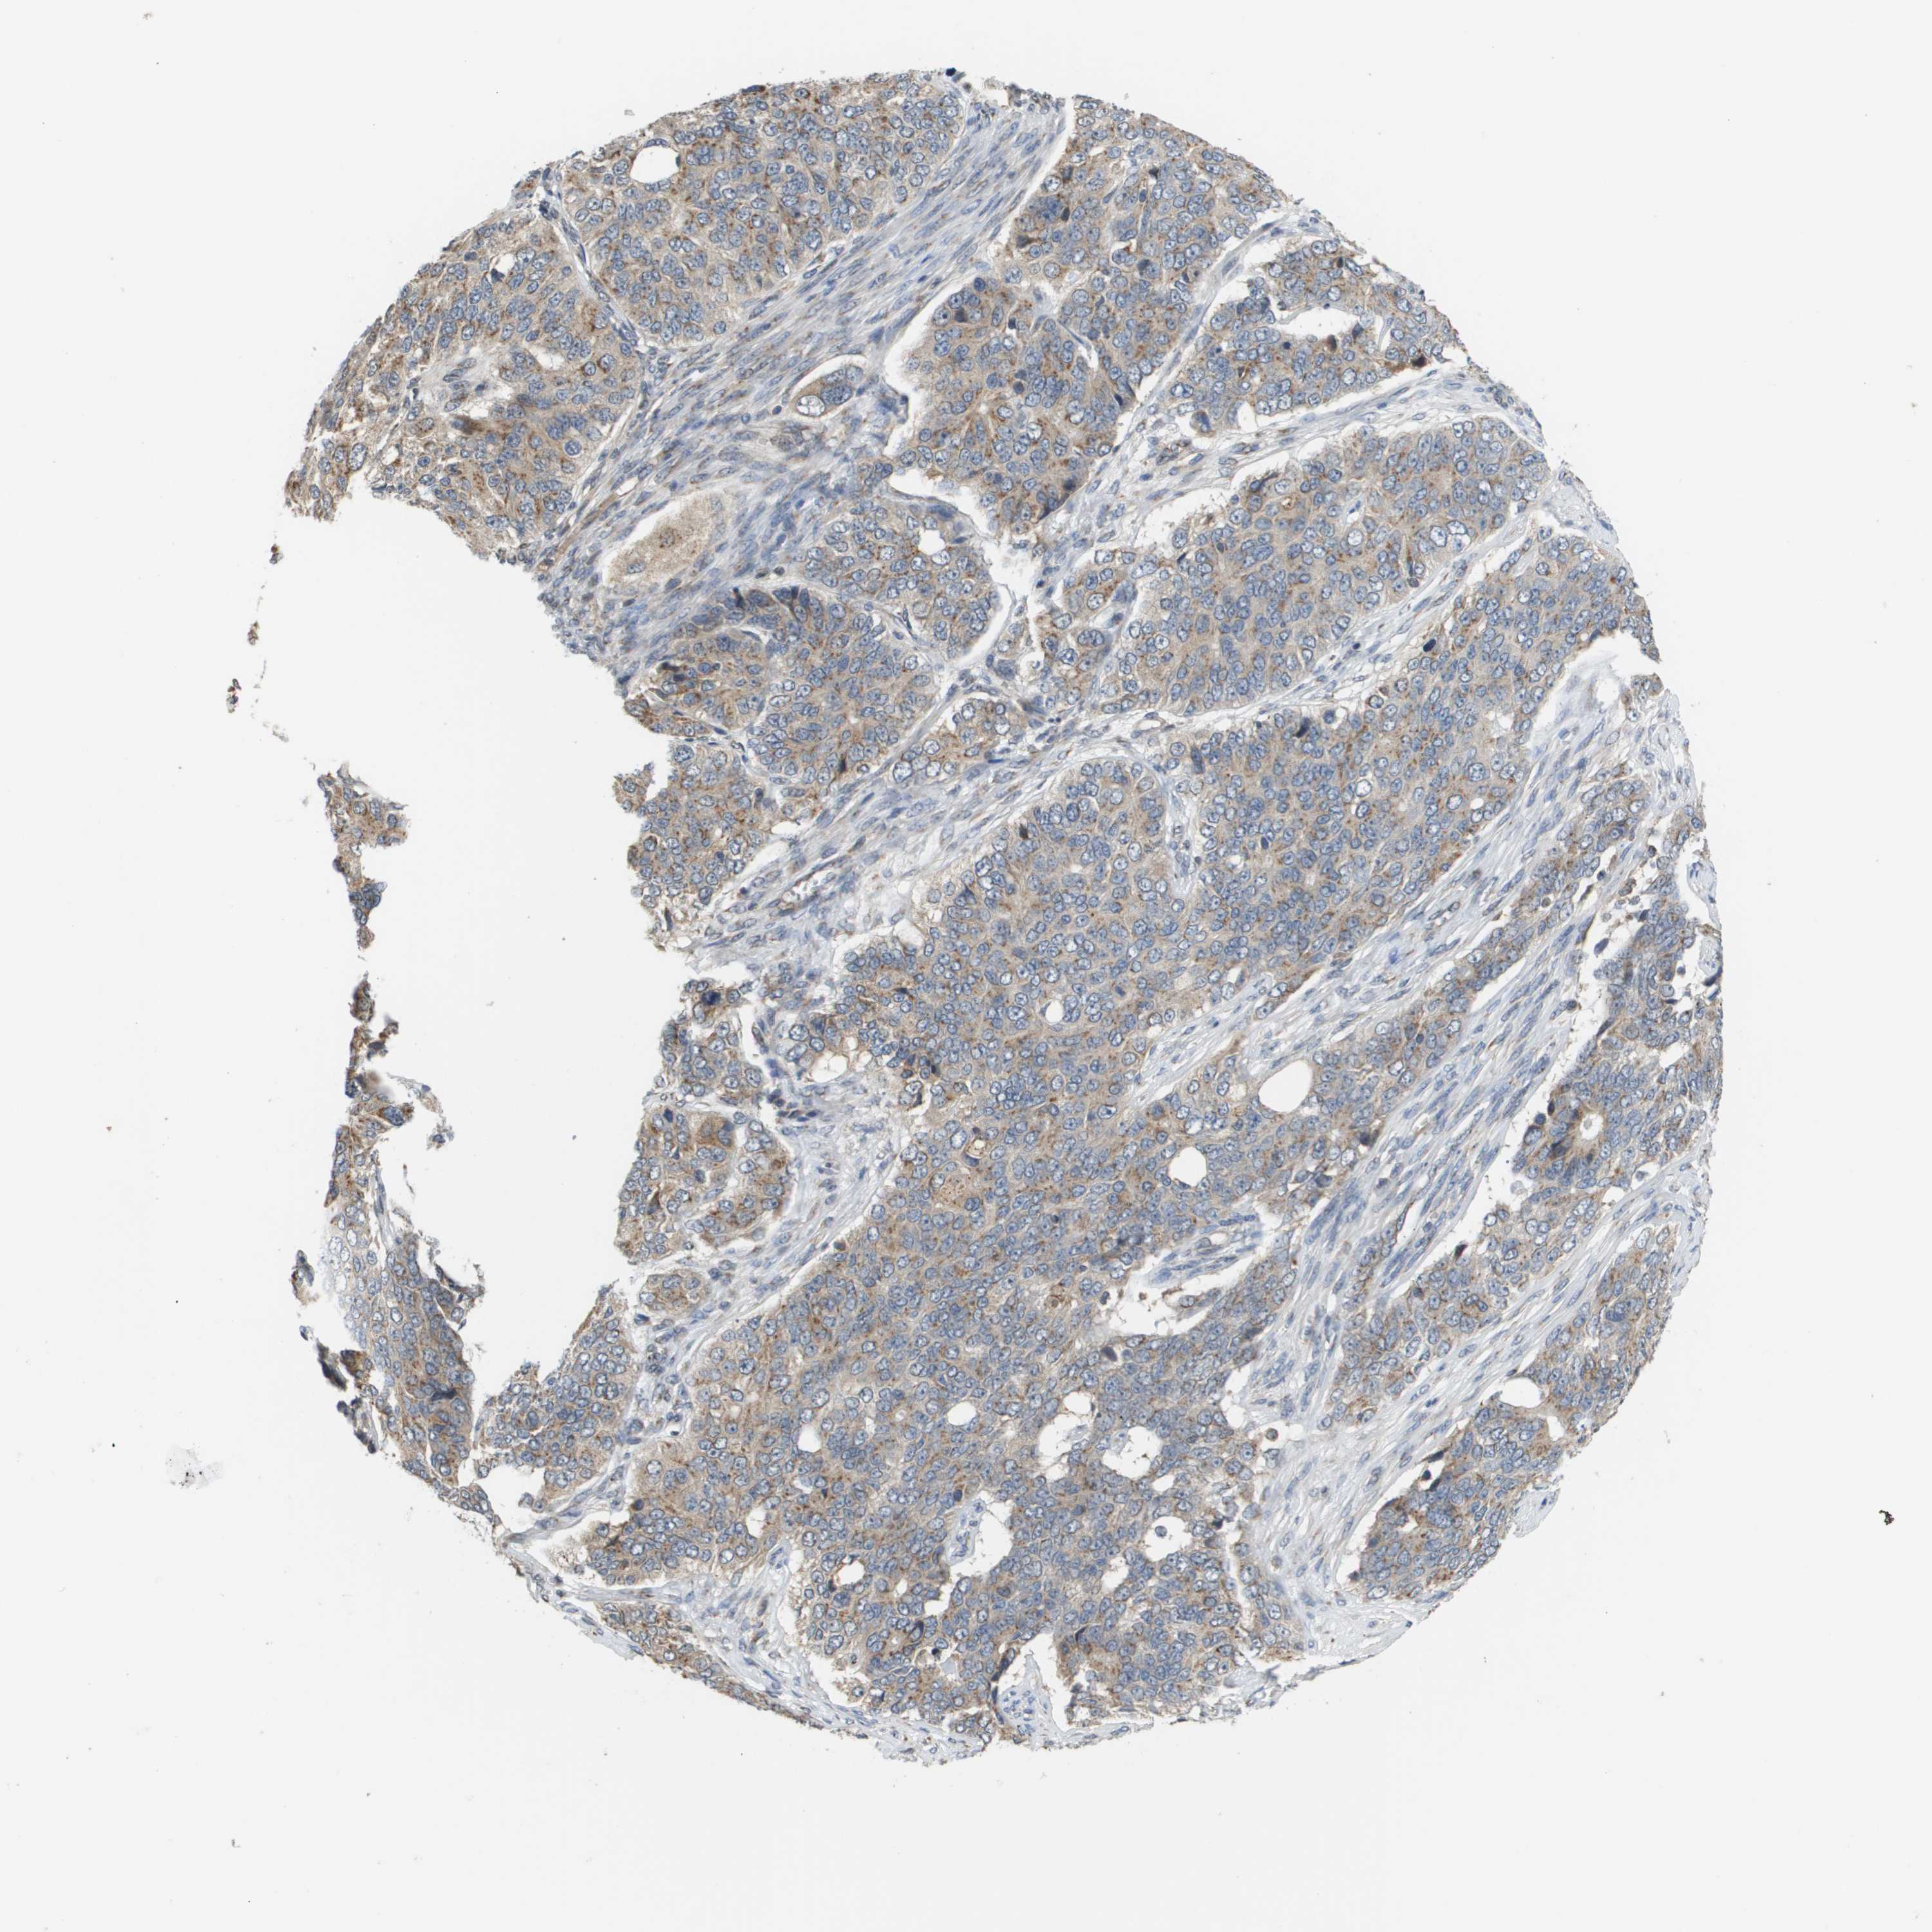

OVARIAN CANCER - Protein expressioni

A mouse-over function shows sample information and annotation data. Click on an image to view it in a full screen mode. Samples can be filtered based on level of antibody staining by selecting one or several of the following categories: high, medium, low and not detected. The assay and annotation is described here.

Note that samples used for immunohistochemistry by the Human Protein Atlas do not correspond to samples in the TCGA dataset.

Antibody stainingi

Antibody staining in the annotated cell types in the current human tissue is reported as not detected, low, medium, or high, based on conventional immunohistochemistry profiling in selected tissues. This score is based on the combination of the staining intensity and fraction of stained cells.

Each image is clickable and will lead to virtual microscopy that enables deeper exploration of all samples and also displays staining intensity scores, fraction scores and subcellular localization as well as patient and tissue information for each sample.

Antibody HPA006277

Antibody HPA006507

Antibody CAB017027

Cystadenocarcinoma, serous, NOS

Cystadenocarcinoma, mucinous, NOS

Carcinoma, endometroid

Carcinoma, NOS